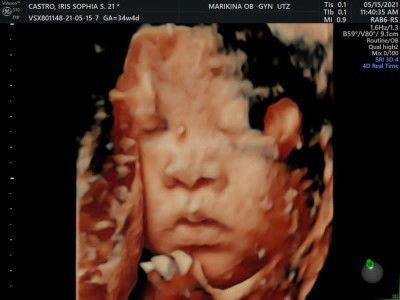

Buti nalang kita pa yung face ni baby ko 😄😊sabi kase ng OB 36weeks masyado na daw malaki si baby baka nakatalikod na sya cephalic na raw kase ang posisyon ni baby so tinry parin namin kase dapat ang Required age para makapag 3/4d. Ultrasound is 27-30 weeks handa ako mag bayad ng kahit mag kano para lang makita na kalagayan ni baby ko sa tummy ko . Kayo ba nakapag try na ba kayo makaag pa 3/4d ultrasound ??? #1stimemom #firstbaby